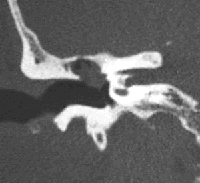

El colesteatoma és un tumor benigne de l’orella format per un cúmul de pell que creix de manera desordenada i progressiva, i que afecta inicialment al timpà i als ossets (martell, enclusa i estrep).

Alguns dels símptomes que produeix són vertigen i pèrdua completa i irrecuperable de l’audició, paràlisi facial (si comprimeix el nervi que mou la cara), meningitis i abscés cerebral, quan envaeix estructures cerebrals, o, si ha evolucionat lliurement i sense tractament, hipoacúsia i supuració.

En general, la seva evolució és lenta i indolora, per això alguns pacients no acudeixen a l’otorinolaringòleg fins que la malaltia ja ha començat a complicar-se. El seu tractament és sempre quirúrgic mitjançant timpanoplàstia. Es tracta d’una operació en què, mitjançant micocirurgia, s’extirpa completament el colesteatoma. En un 90 % dels casos els resultats són un èxit, especialment si el tumor es troba en un estadi inicial.

A causa de la tendència que té a reproduir-se, el pacient ha de ser controlat durant molts anys, en la majoria dels casos, mitjançant una visita anual i, més rarament, cada sis mesos. D’altra banda, a més de l’extirpació completa del colesteatoma, aquesta operació busca conservar tant com es pugui l’audició existent i, en la mesura del possible, també la recuperació de la pèrdua mitjançant la reconstrucció dels ossets de l’orella mitjana o ossiculoplàstia, malgrat que de vegades no sigui possible.